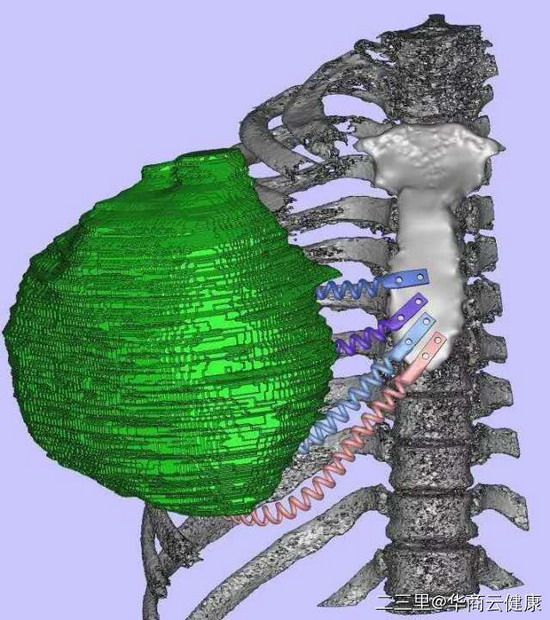

25岁男子右胸生长巨大肿瘤,医生讲解患者切除肿瘤胸壁三维重建治疗方案

25岁男子右胸生长巨大肿瘤如“篮球”大小,医生手术为其切除巨大肿瘤。 唐都医院供图

3D打印建模

胸腔外科与3D打印中心联合会诊后,决定为小田定制3D打印钛合金弹性肋骨。曹铁生教授介绍说,人体的胸肋关节属于微动关节,会随着呼吸起伏。个体定制、量体裁衣的3D打印弹性胸肋骨更加贴合人体肋骨曲度与力学性能,弹性设计使患者在术后生活及呼吸运动不受限制,更有利于保护胸腔脏器。而且植入的4根3D打印弹性胸肋骨共87克,质量轻,患者也无负担。